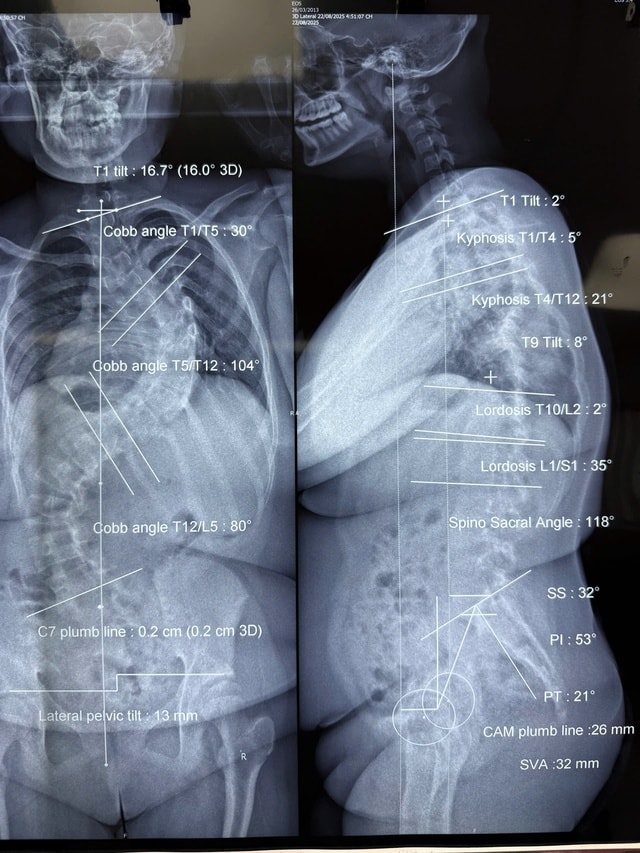

Trường hợp đầu tiên là bé M.N.C.L. (12 tuổi, ngụ huyện Hóc Môn). Tình trạng vẹo cột sống của bệnh nhi tiến triển nhanh bất thường. Tại thời điểm phẫu thuật, trẻ có hai đường cong lớn, trong đó đường cong chính vẹo 104 độ và đường cong thứ hai 80 độ. Trong 7 tháng chờ mổ, cấu trúc cột sống tiếp tục biến dạng nhanh và nặng.

Trường hợp thứ hai là bé Y.T. (13 tuổi, Quảng Ngãi), khi nhập Bệnh viện Nhi đồng 1, bé đã vẹo 128 độ kèm gù 108 độ.